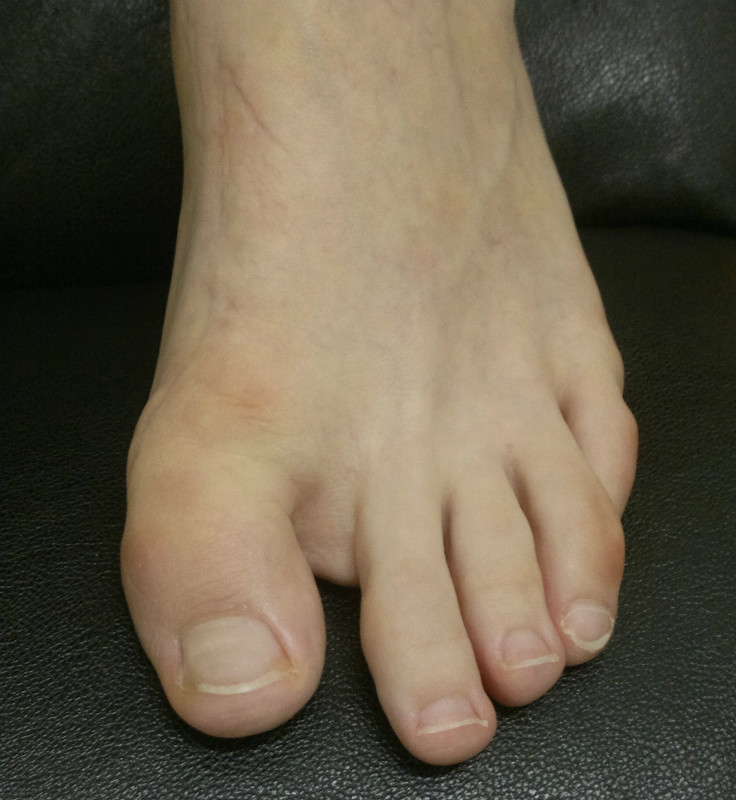

С Наступающим Новым Годом! Обратилась пациентка 42лет, 4 года назад оперирована в Боткинской. Левая стопа не беспокоит, в правой  при ходьбе боли в 1 плюснефаланговом суставе, неудобство при ношении обуви, "косметика смущает"..При осмотре: подвывих 1 пальца, вправляется, нестабильный. Что можно предложить? Релиз из латерального доступа и попробовать укрепить капсулу с медиального доступа  имитируя коллатеральную связку, основную фалангу временно зафиксировать в вправленном положении спицей недельки на 3-4? Спасибо!                                                                                                          PS:  В Боткинскую не хочет, доктор говорит была пожилая, сказала "не знаю чем помочь". Присылаю картинки...